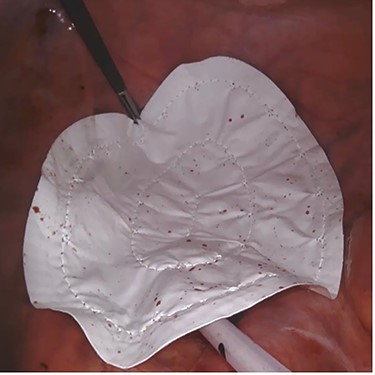

We present five cases where pelvic closure was performed using Gore-Tex Dual Mesh (WL Gore & Associates, Inc., Newark, DE, USA) in fully laparoscopic and robotic-assisted approach to reduce the risk of small bowel descent. All cases were performed by a single consultant colorectal surgeon between November 2019 to December 2020. After adhesiolysis and bowel resection, small bowels were placed in abdominal cavity. Gore-Tex Dual Mesh (10 × 15cm) placement at the pelvic inlet was performed laparoscopically in all cases except 1 with robotic assistance. The microporous smooth surface faced the abdominal cavity and the macroporous rough surface faced the pelvic cavity. The mesh was anchored to sacral promontory, pelvic brim and lateral peritoneum using tacker and reinforced intracorporeally with polypropylene 2/0 or endoclip with 1.0–1.5 cm gap between the sutures. The mesh was extended 2–3 cm beyond the edge of pelvic inlet. Placement of the mesh took an additional 30 minutes of operating time. Pelvic drain was inserted either transabdominally or transanally. Follow-up included history of bowel obstruction after surgery or evidence of small bowel descent within the pelvis from CT abdomen performed for evaluation of disease. Wound infection and other surgical related complications were also assessed.

A 42-year-old man with perianal abscess and fistula due to low rectal cancer had completed long-course radiotherapy but was unable to complete FOLFIRI regimen due to elevated liver enzymes because of his underlying chronic hepatitis B. He underwent robotic-assisted abdominoperineal resection (APR) 6 weeks later. Mesh placement was performed laparoscopically after placing transabdominal pelvic drain (Fig. 1). He developed perineal wound infection on postoperative day 4 requiring wound dressings and antibiotics. He was discharged 17 days after surgery but was readmitted 28 days after initial operation for presacral abscess requiring percutaneous drainage. Subsequent CT abdomen showed resolution of presacral collection. Histopathological examination showed moderately differentiated adenocarcinoma ypT3N0M0. He completed adjuvant capecitabine and after 12.5 months, there was no evidence of unhealed perineal wound or small bowel descent.

Case 2—laparoscopic picture of Gore-Tex Dual Mesh placed at the pelvic inlet with the microporous smooth side facing the abdominal cavity.